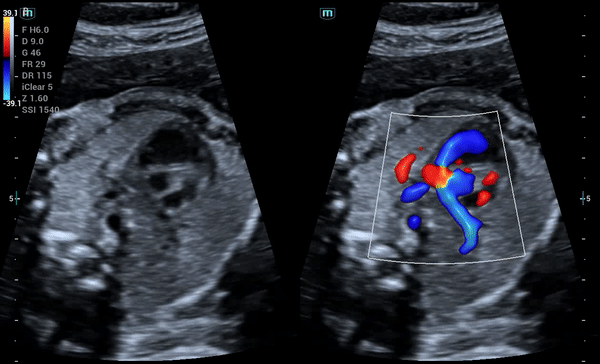

Высокоточная гемодинамика HR Flow™

Технология Mindray отображает кровоток с бо́льшим пространственным и временным разрешением даже в случае исследования мелких сосудов.

Чёткое отображение малых и перекрывающихся сосудов

Glazing Flow – метод цветового/энергетического доплеровского потока с 3D-визуализацией, дополняющий исследование гемодинамики и структуры малых и перекрывающихся сосудов.